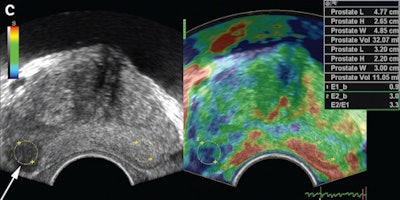

The study included 69 patients with focal lesions that were found on transrectal sonography. The individuals were referred for transrectal ultrasound-guided prostate biopsy between June 2012 and August 2013. A uroradiologist with 14 years of experience performed all transrectal ultrasound and elastography studies on a Logiq E9 ultrasound scanner (GE Healthcare) with a 5- to 9-MHz multifrequency endocavitary probe.

The uroradiologist used a sector transducer to perform elastography for the patient's most suspicious focal lesion. The lesion's strain index was automatically calculated by dividing the strain ratio of a normal-looking area of tissue by the strain ratio of the focal lesion. All patients then received systematic 12-core randomized biopsies as well as two targeted biopsies. Of the 69 patients, 31 (44.9%) were found to have prostate cancer.